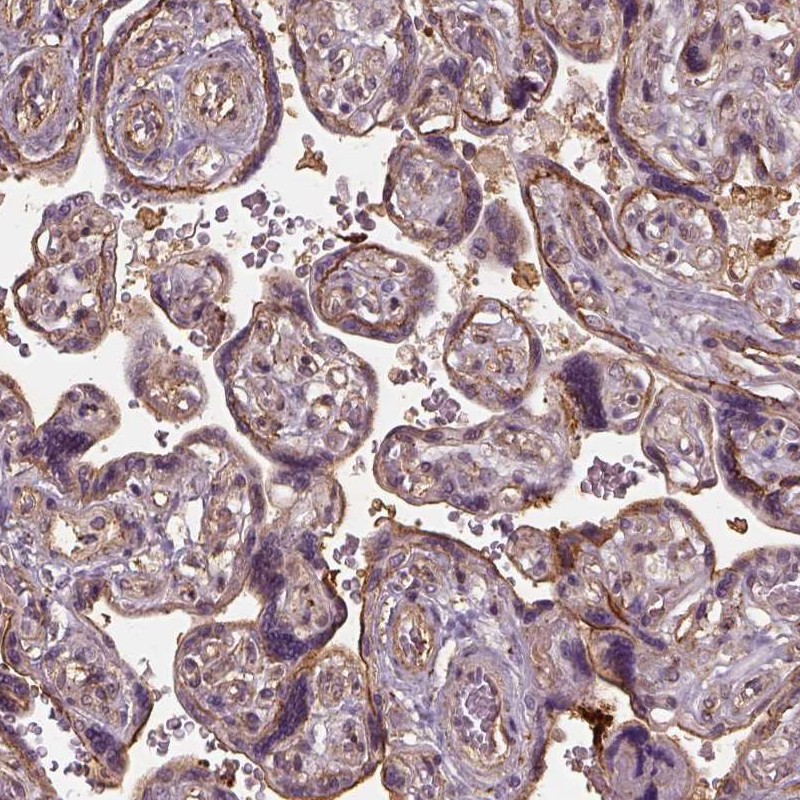

Immunohistochemical staining of human placenta shows strong membranous positivity in trophoblastic cells.